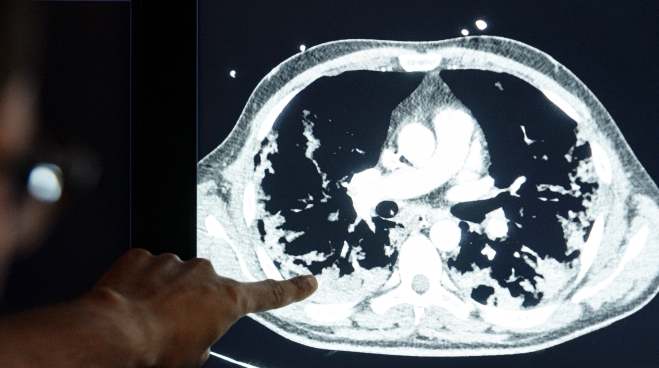

Healthcare professionals at Leiden University Medical Centre can now use artificial intelligence to quickly and easily calculate whether a corona patient has suffered serious lung damage.

Our CAD4COVID software will help to assess affected lung tissue in COVID-19 patients.